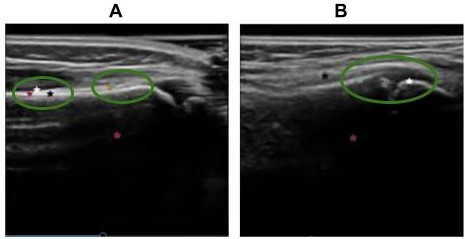

In affected as well as unaffected wrists the neural networks correctly identified the top portion of the bone with multiple keypoints (refer Figure 2). In affected wrists (Figure 2B) the network was able to track keypoints near the fracture. We manually selected a tight rectangular region of interest around the bone and the neural network correctly identified key points within this region in 180 / 250 ultrasound frames.

Refer to caption

Figure 3: Example of slices in which the neural network correctly identifies keypoints along the boundary of the bone. A: Intact bone imaged in the Volar Sagittal(VS) view B: Ultrasound frame capturing the fracture in the VS view. Note that the network identified points near the bone discontinuity indicating fracture.